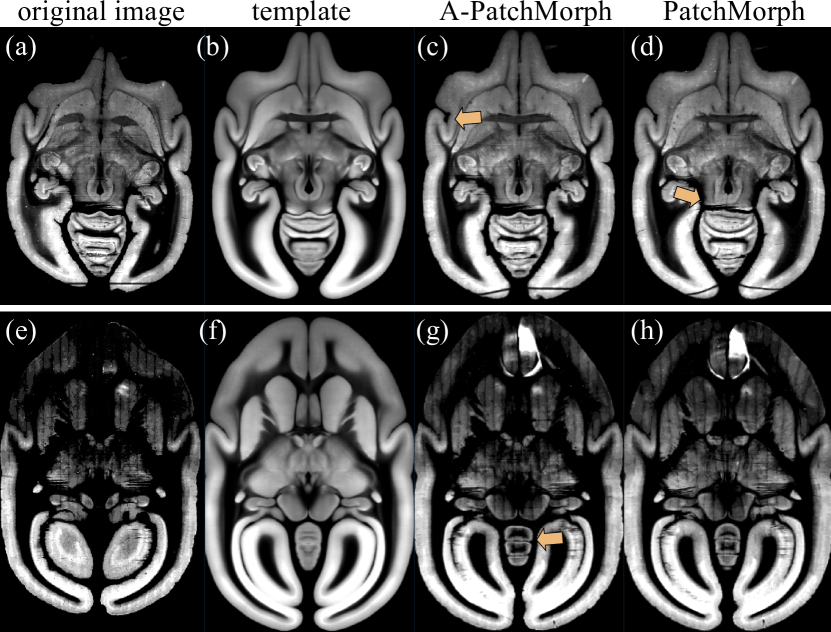

Refer to caption

Figure 12: Two challenging examples from the marmoset brain image experiment are depicted here, highlighting issues with missing coronal sections (upper example) and persistent tracer signals (lower example). Each image displays a cross-section from a 3D dataset. The first column shows a section from the original image, followed by a section from the target template in the second column. The last two columns present sections from the moved images using the local affine A-PatchMorph and the PatchMorph architectures, respectively. A-PatchMorph tends to preserve minor irregularities and spatial differences post-alignment (see panels (c) and (g)). In contrast, PatchMorph is more adaptive and can smooth out such irregularities; however, it may also inappropriately close gaps caused by tissue damage, potentially leading to incorrect deformations, as illustrated in panel (d).

The Marmoset dataset poses an out-of-distribution challenge, with artifacts not fully represented in the training set. In this experiment, we compared PatchMorph against ANTs results from [21], using the same 323superscript32332^{3}32 start_POSTSUPERSCRIPT 3 end_POSTSUPERSCRIPT patch size for both PatchMorph and its variant, A-PatchMorph, as in the Mindboggle dataset. To address misalignments due to tracer signal leakage and contrast differences, we employed a mutual information (MI) loss from MONAI during training, replacing the cross-correlation metric. Additionally, we implemented a localized MI loss by dividing patches into 83superscript838^{3}8 start_POSTSUPERSCRIPT 3 end_POSTSUPERSCRIPT sub-cubes and averaging their MI values, each loss weighted equally at 0.5.

The results, presented in Table 4, show that both PatchMorph versions achieved comparable Dice scores around 0.89. However, further scrutiny revealed unique challenges: the standard PatchMorph occasionally over-stretched tissues to compensate for damage or missing sections (Fig. 12, panel (a)), whereas A-PatchMorph’s reliance on local affine transformations made it less susceptible to artifacts but also less adept at smoothing irregular tissue boundaries (Fig. 12, panel (c) and (g)). An invertibility analysis of the warp fields, similar to that conducted for the MindBoggle dataset (refer to Table 3), indicated no significant issues.